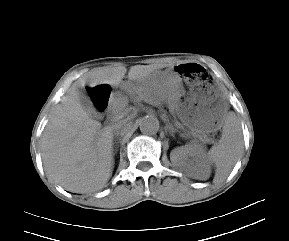

标题: CT19533:病变来源于哪?

患者,男,发现上腹部包块两月余。

病变位于肝胃间隙,实际就是位于小网膜囊(左肝下后间隙),呈轻度不均匀性强化,腹腔内及腹膜后见多发肿大淋巴结。所以我考虑肝胃间隙恶性胃肠间质瘤并淋巴结转移。

病灶强化不显著,灶周及腹膜后见多量淋巴结肿大,考虑淋巴瘤可能,其次考虑间质瘤

病灶与胰腺分界不清,来源于胰腺?

强化后病变与胃壁分界清楚,并且血供不是来源胃壁血管。考虑胰腺颈体癌并腹腔腹膜后淋巴结转移。